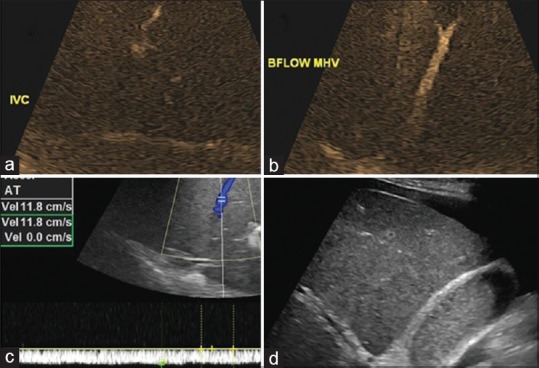

However, subsequent liver ultrasound with color Doppler [Figure 2] showed low-velocity flow in hepatic veins and portal veins with no evidence of filling defects to suggest venous thrombosis. Hepatic vein lumen was patent. Due to an elevated PT-INR (1.9) and borderline platelet count (1.4 lakhs), percutaneous liver biopsy was deferred, and transjugular liver biopsy with hepatovenous pressure gradient assessment was considered to rule out any membranous obstruction due to Budd–Chiari syndrome.

| Figure 2:Ultrasound liver with Doppler showing, (a) B-flow imaging showing patent inferior vena cava and left hepatic veins, (b) patent middle hepatic flow, (c) color Doppler images of the right hepatic veins showing hepatofugal patent flow with attenuated phasicity, (d) ultrasonography of liver showing heterogenous echotexture of parenchyma with ascites and cholestasis